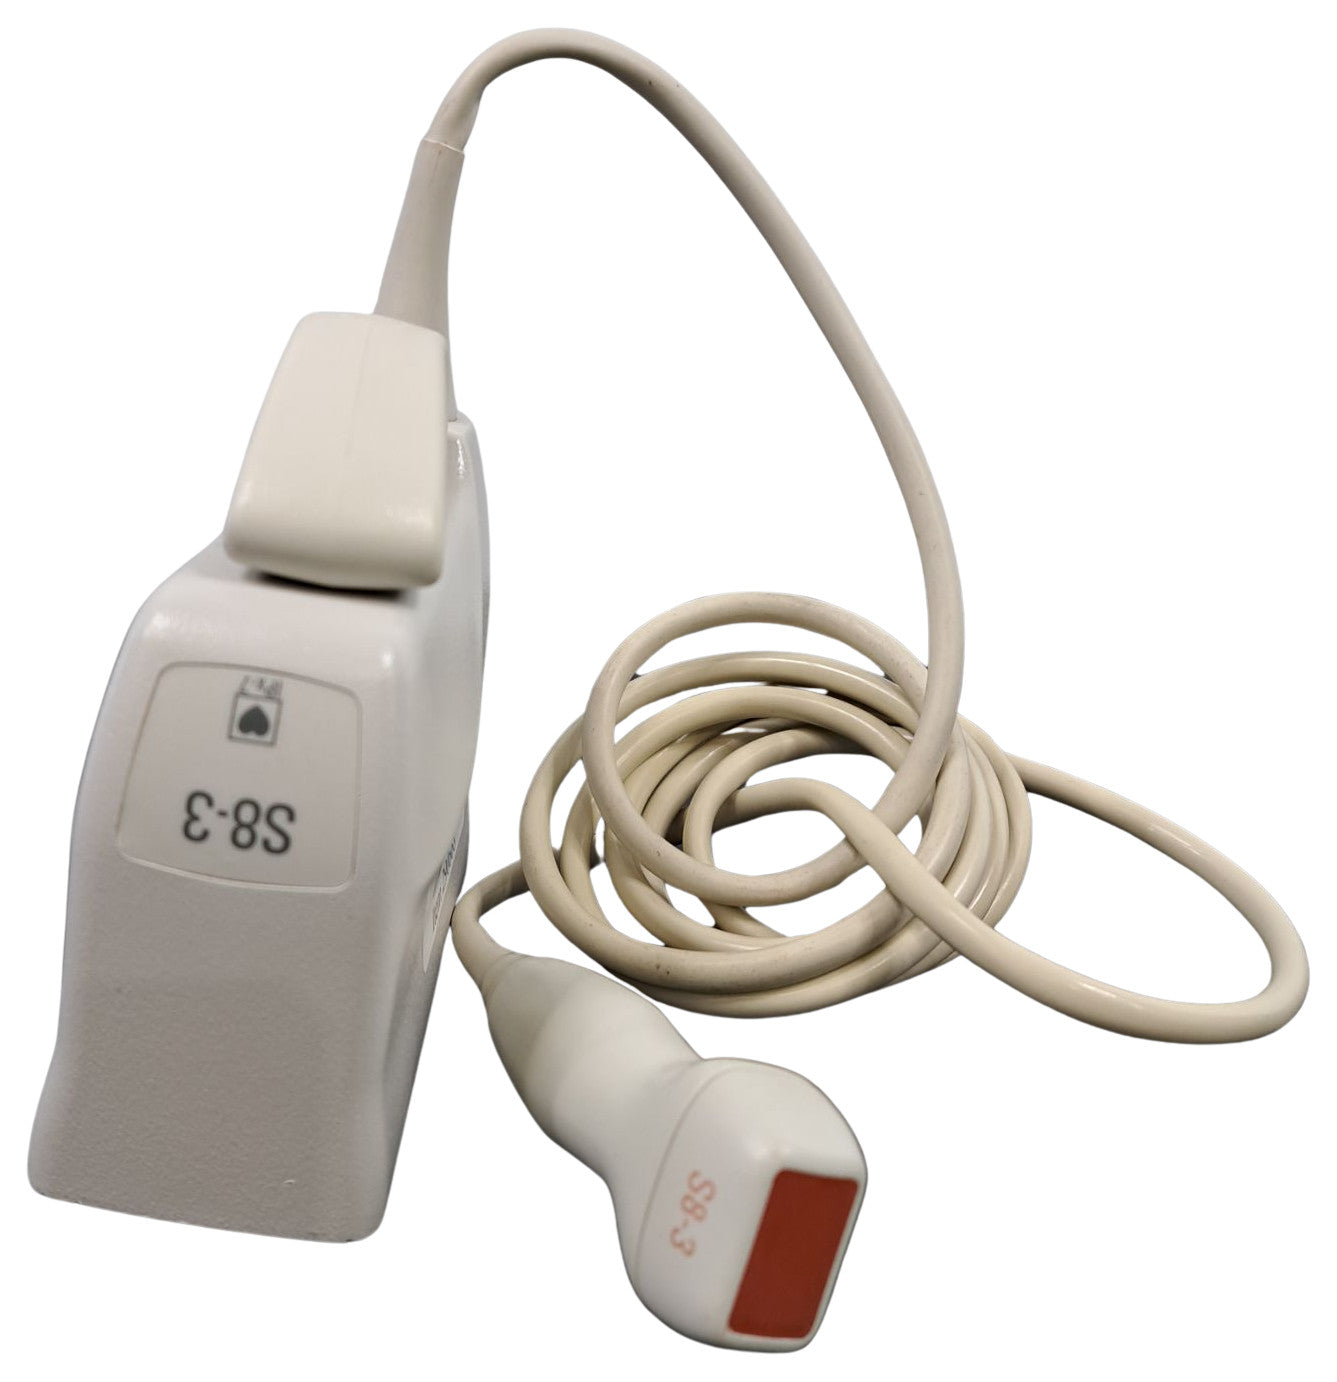

Brand

Philips

MPN

S8-3

SKU

S8-3__290668

Probe is in good condition no compatible ultrasound to test the item. For the power cord, if you see a separate picture of the power cord, you'll receive it. Otherwise, we used the power cord only to test the item.